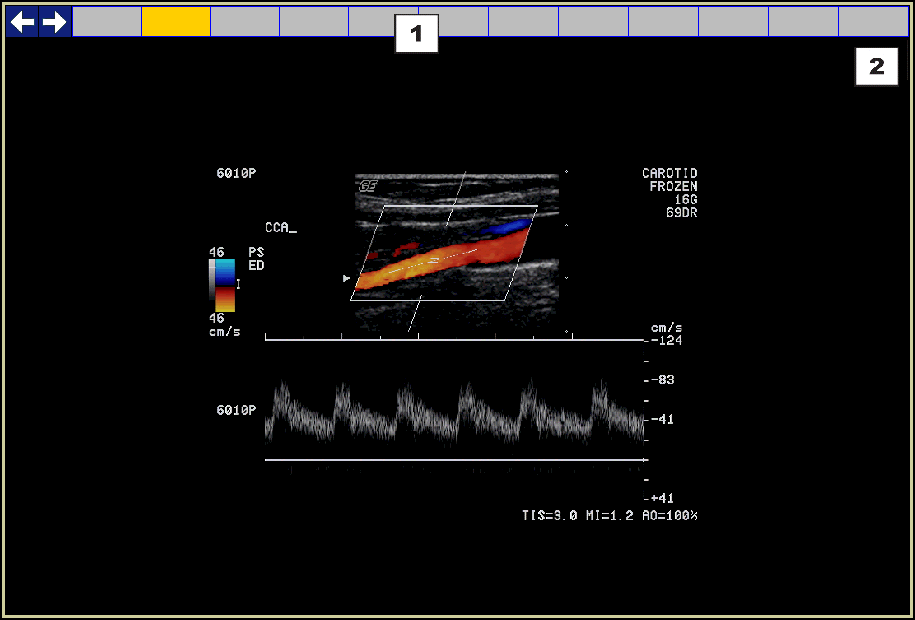

Part of the screen that displays the actual images of a series. |